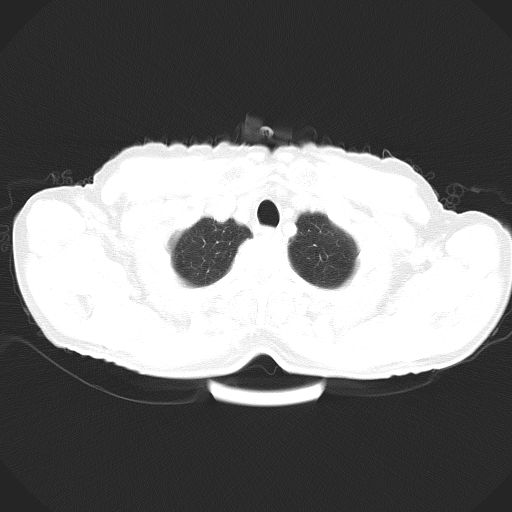

以下是引用心路寻觅在2010-3-1 10:23:00的发言:[br]1、考虑左肺上叶周围型肺癌[br]2、右上肺陈旧性病灶。[br][br][本贴已被 心路寻觅 于 2010-3-1 10:40:18 修改过]

以下是引用shuiyuan在2010-3-1 10:45:00的发言:[br]考虑左肺上叶中心型肺癌伴阻塞型炎症,邻近胸膜受侵。